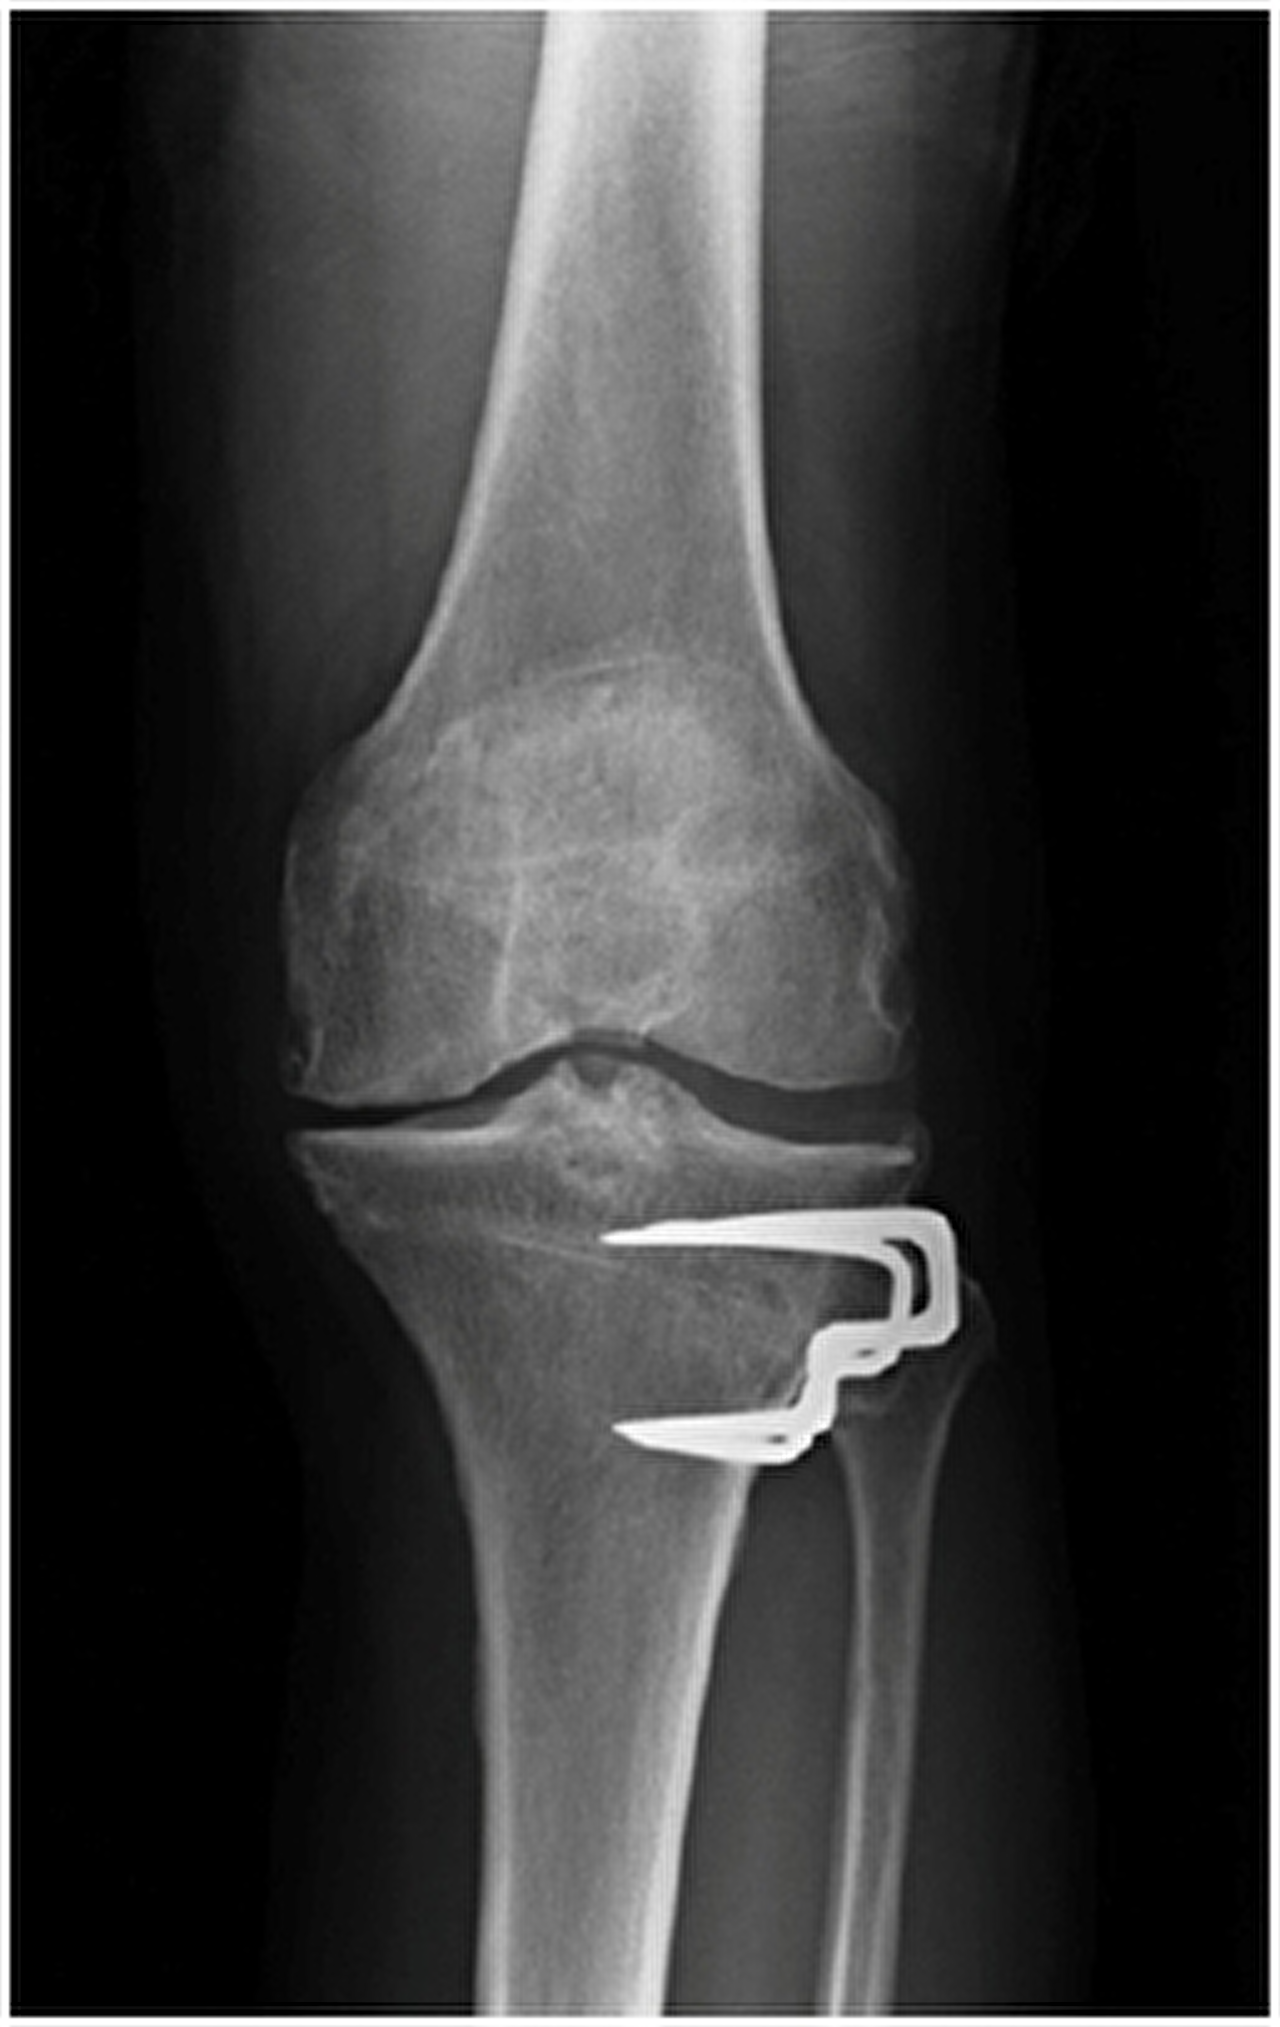

Röntgenfoto vooraanzicht knie na tibiakop osteotomie.

Fixatie door middel van plaat en schroeven.

Fixatie door middel van krammen.